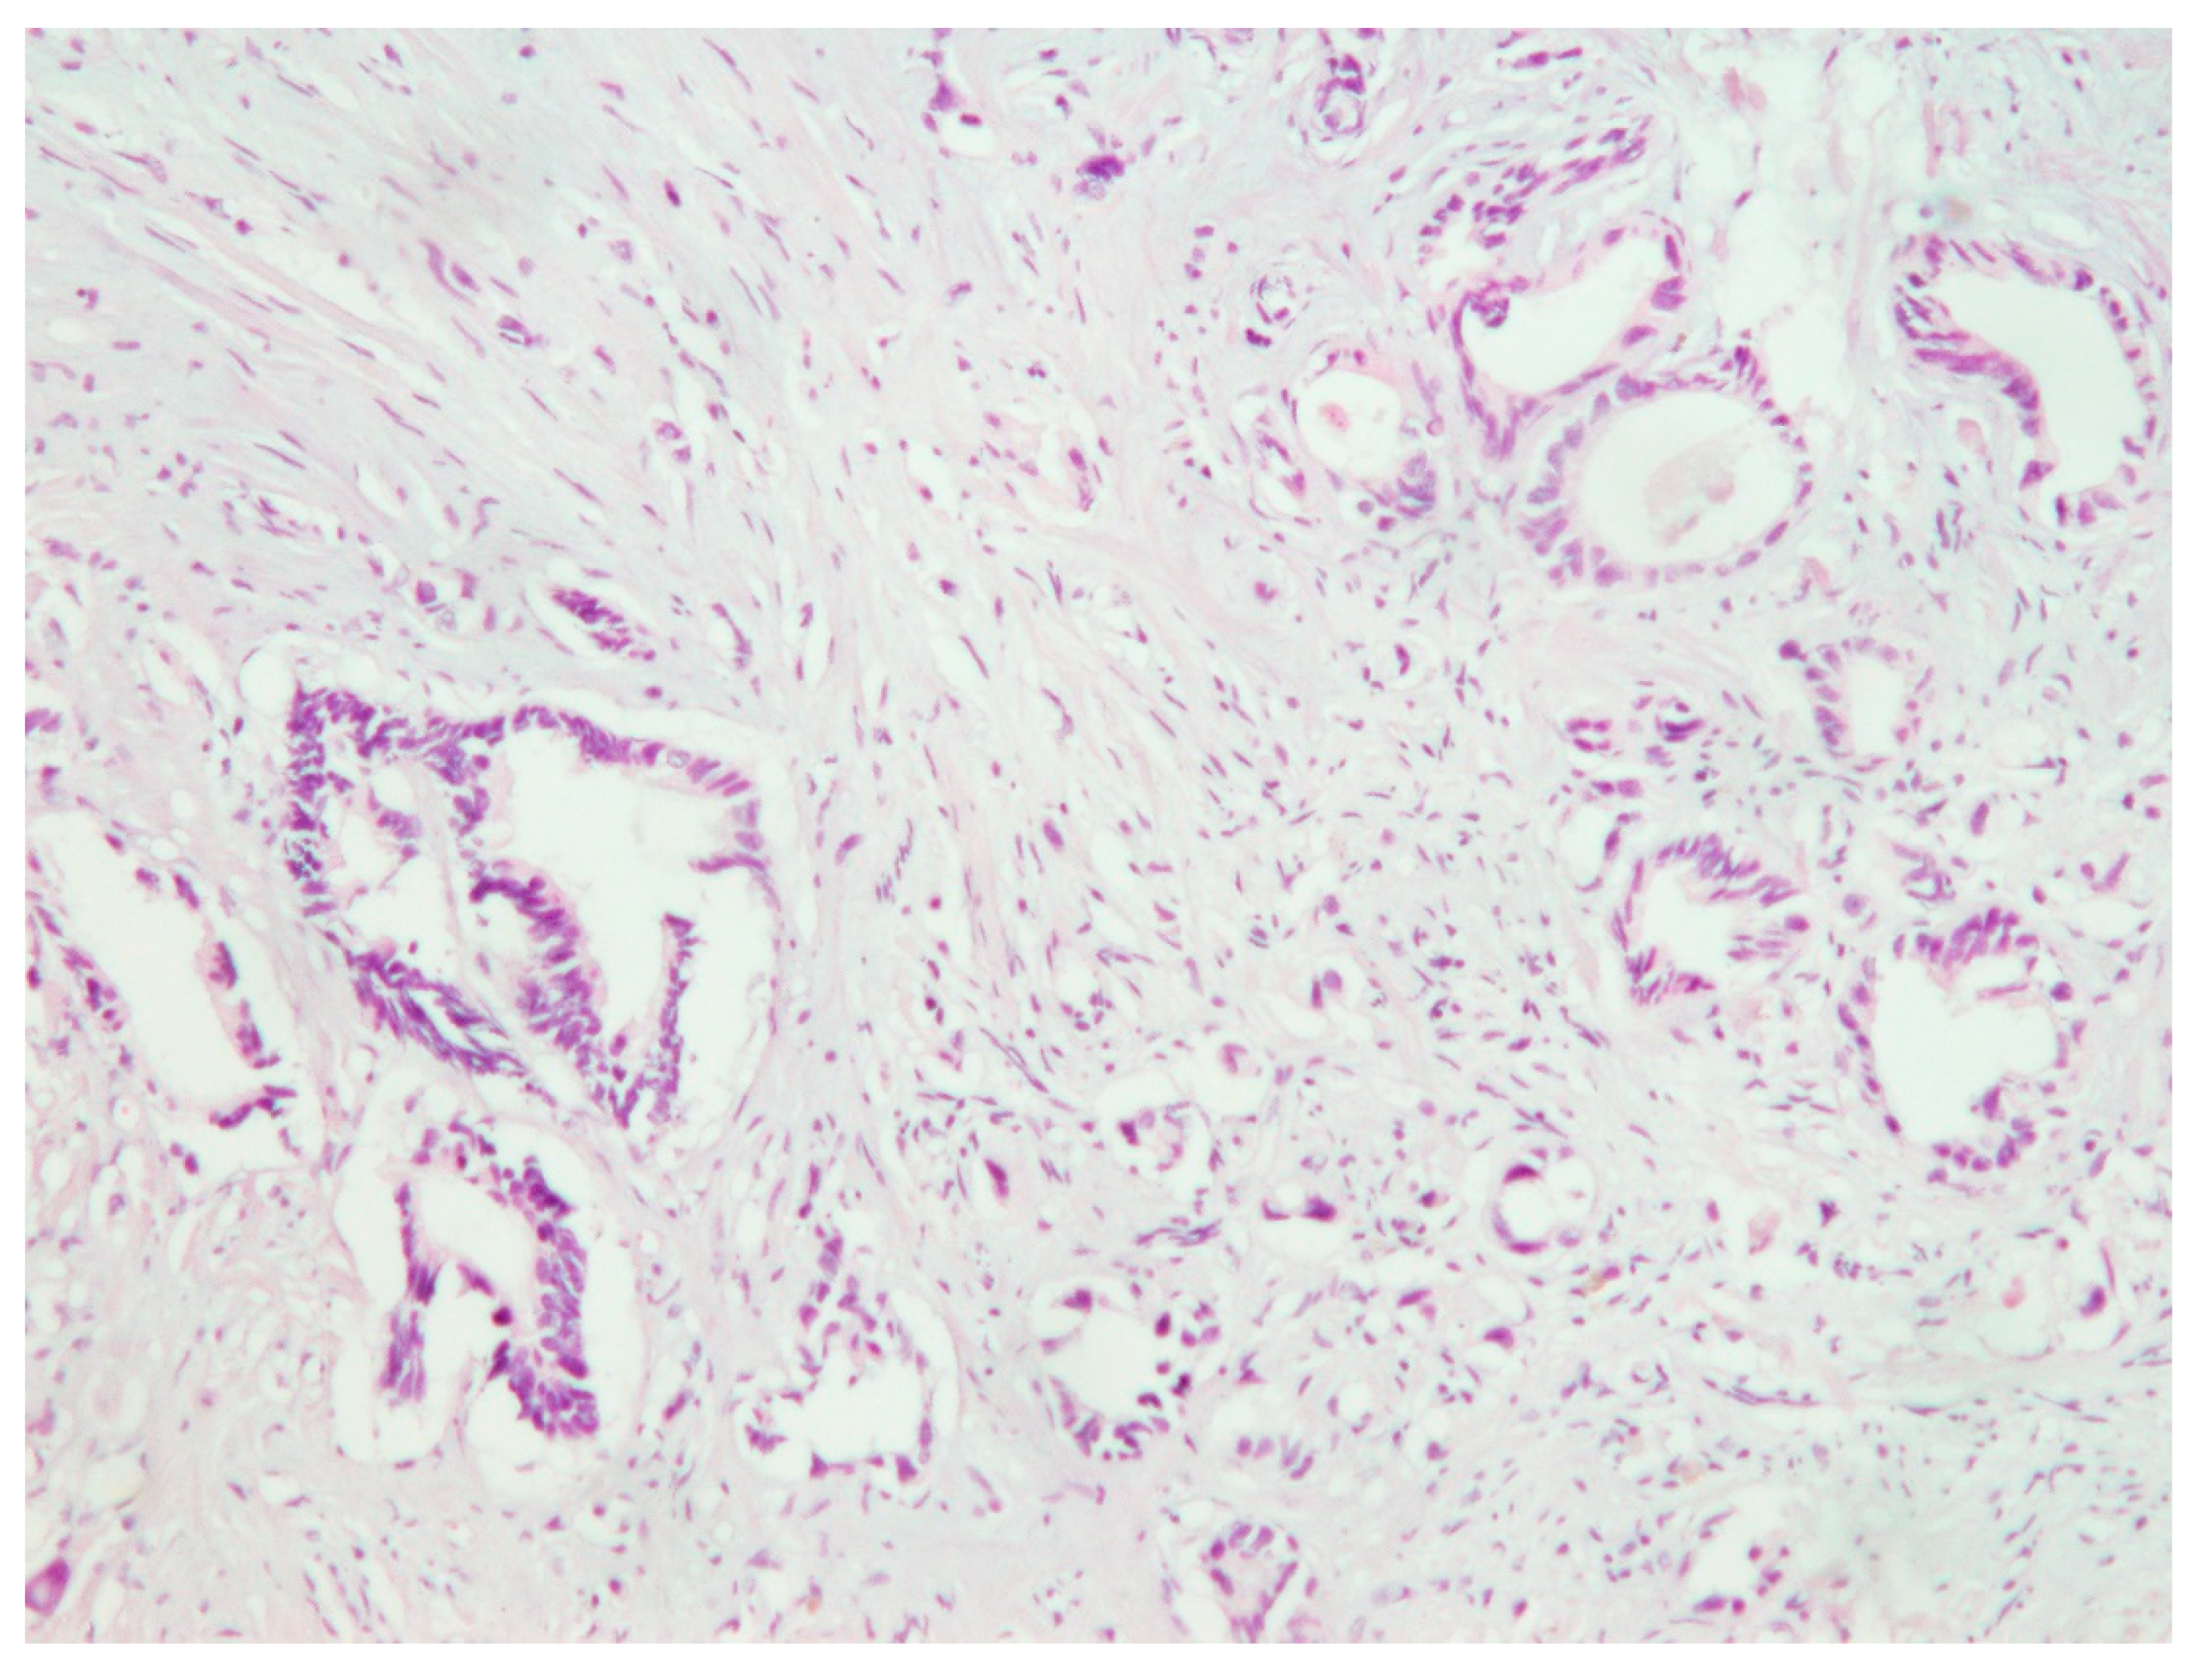

Pancreatic Carcinoma Metastatic to the Gingiva

2. Case Report